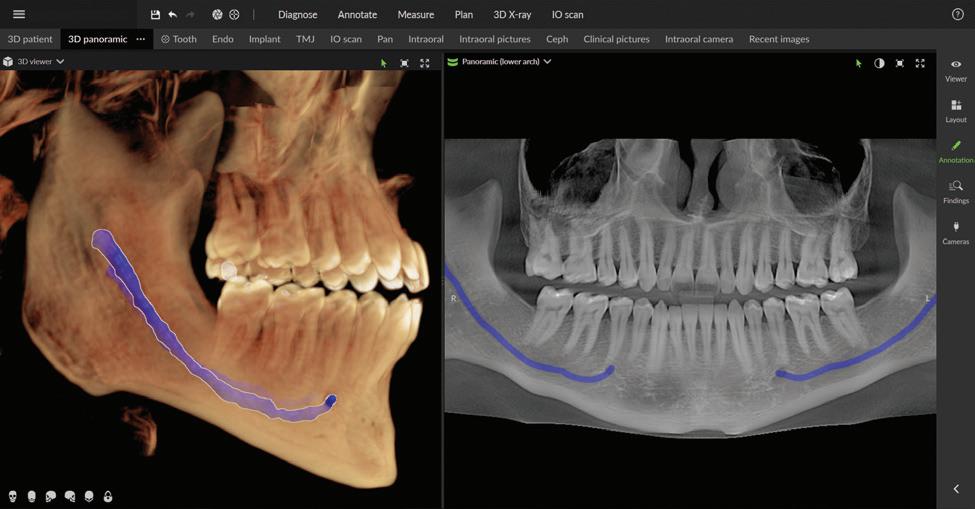

The next generation of DEXIS™ Cone Beam Technology is here

Simplify and expand your 3D diagnostics with the new ORTHOPANTOMOGRAPH™ OP 3D™ LX

Leading innovator of dental imaging technologies, DEXIS, has launched the next-generation OP 3D.

Built on OP 3D technology, the OP 3D LX imaging platform expands your 3D diagnostic capabilities with a wide range of clinical applications that support your evolving practice and enhance diagnostic confidence.

Consistent, high-quality images

Seamless integration with new DTX Studio™ Clinic software

P acked with AI-assisted software features, DTX Studio™ Clinic complements OP 3D LX in numerous ways—for example, correcting patient positioning errors and detecting

Figure 4. Maxillofacial surgery. Figure 6. TMJ analysis. Figure 8. Airway analysis. Figure 10. Periodontics. Figure 5. Orthodontics. Figure 7. Implant placement. Figure 9. Prosthodontics. Figure 11. Endodontics.

landmarks, annotating mandibular nerve canals, tracing patientspecific panoramic curves for mandible and maxilla and merging CBCT and intraoral scan data for improved implant planning. These intuitive award-winning software features support a more efficient workflow allowing you to spend less time in the software and more time with your patient.

Figure 12. Merge CBCT and intraoral scans. Figure 13.Automatic focal trough. Figure 14. Mandibular nerve canal annotation. * Optional field of view.